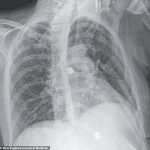

X-ray scans conducted during her stay uncovered small nodules in her lungs, a finding suggestive of bacterial infection.

Further imaging revealed lesions in multiple organs, including the liver, lymph nodes, pancreas, and brain—indications of a systemic infection.

After nine weeks of testing, including biopsies and bacterial cultures, doctors confirmed the presence of *Mycobacterium tuberculosis*, the pathogen responsible for tuberculosis (TB).

This diagnosis marked a rare but severe case of disseminated TB, a form of the disease that spreads beyond the lungs to affect multiple organs.